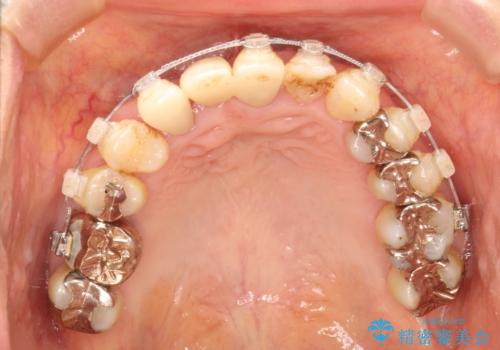

矯正を併用した前歯のセラミックブリッジ治療

- 上顎前歯をきれいにしたいとのことで来院されました。

レントゲンを撮影すると保存が難しい歯がありました。

またがたつきの度合いから歯を1本抜歯して矯正治療を行いセラミックブリッジを装着することで、審美的・機能的改善を行う計画としました。

治療の順序は

①保存不可の歯の抜歯・根管治療

②矯正治療

③セラミックの装着

という流れで行いました。

1年程度の治療期間が必要となりましたが、仕上がりには患者様に満足していただけました。